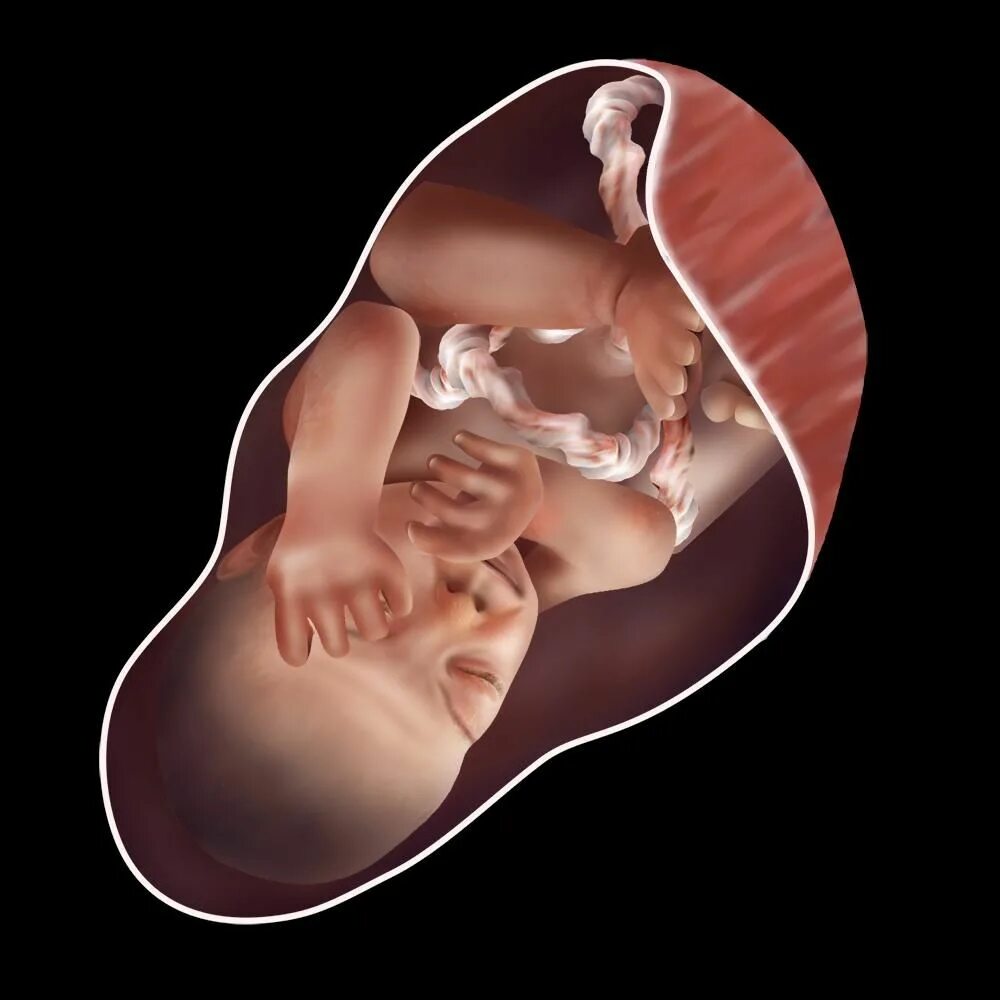

Как выглядит ребенок в 34 недели